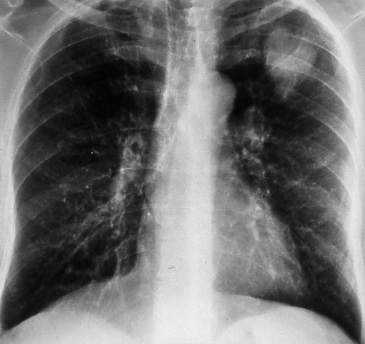

Fig. 36a: Posterior-anterior chest radiograph of a 4 cm. left upper lobe bronchogenic carcinoma. The lymph nodes and visceral pleura were not involved, T2 N0 M0, Stage IB.